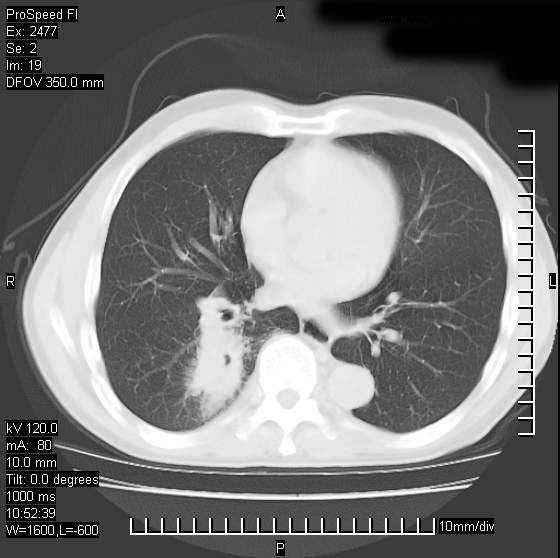

以下是引用天南地北在2007-10-9 14:29:00的发言:[br]1:右上肺结核[br]2:右肺下叶肿块:不支持肺癌,首先考虑炎性病变-肺脓疡可能性大[br]理由:1:临床病史支持,肺脓肿症状不明显应该是不规则服药造成。[br] 2:肿块边缘模糊,周围可见炎性渗出,长毛刺,内见支气管征,不过有点不规则。[br] 我感觉下肺癌这个诊断有点偏左,建议积极抗炎治疗后复查

以下是引用卜一在2007-10-9 15:55:00的发言:[br][br] [br] 1:右上肺结核[br]2:右肺下叶肿块:不支持肺癌,首先考虑炎性病变-肺脓疡可能性大[br]理由:1:临床病史支持,肺脓肿症状不明显应该是不规则服药造成。[br] 2:肿块边缘模糊,周围可见炎性渗出,长毛刺,内见空气支气管征,不过有点不规则。[br] 我感觉下肺癌这个诊断有点偏左,建议积极抗炎治疗后复查![br]支持! [br] [br] [br]

以下是引用wxy7406在2007-10-9 21:02:00的发言:[br]结合临床病史首先考虑感染性病变,但周围型肺癌不能除外,1.患者年龄偏大2.临床有咯血3.(也觉得是最重要的一点)病灶内有偏心性空洞。

以下是引用王仕学在2007-10-9 13:48:00的发言:[br]右下肺周围性肺癌可能性大,最好活检吧

以下是引用hhcckk在2007-10-9 15:18:00的发言:[br]右上肺病灶考虑结核,病灶多种形态并存(纤维化、增殖性病灶并存)[br]右下肺病灶比较难说,个人意见更趋向于“天南地北”的诊断----肺脓肿[br]1、病人有明显的寒战,高热,肿瘤病人很少出现[br]2、病灶周围的肺纹理走向柔和,没有肿瘤病灶常见的集束征[br]3、病灶边缘的毛刺较长,恶性肿瘤多为短毛刺[br]痰中血丝和病人的年龄是两个不利于良性肿块的因素,建议早点活检

以下是引用ydx_74在2007-10-9 15:53:00的发言:[br]右上肺结核,右下中心性肺癌可能大,肺门淋巴结肿大。